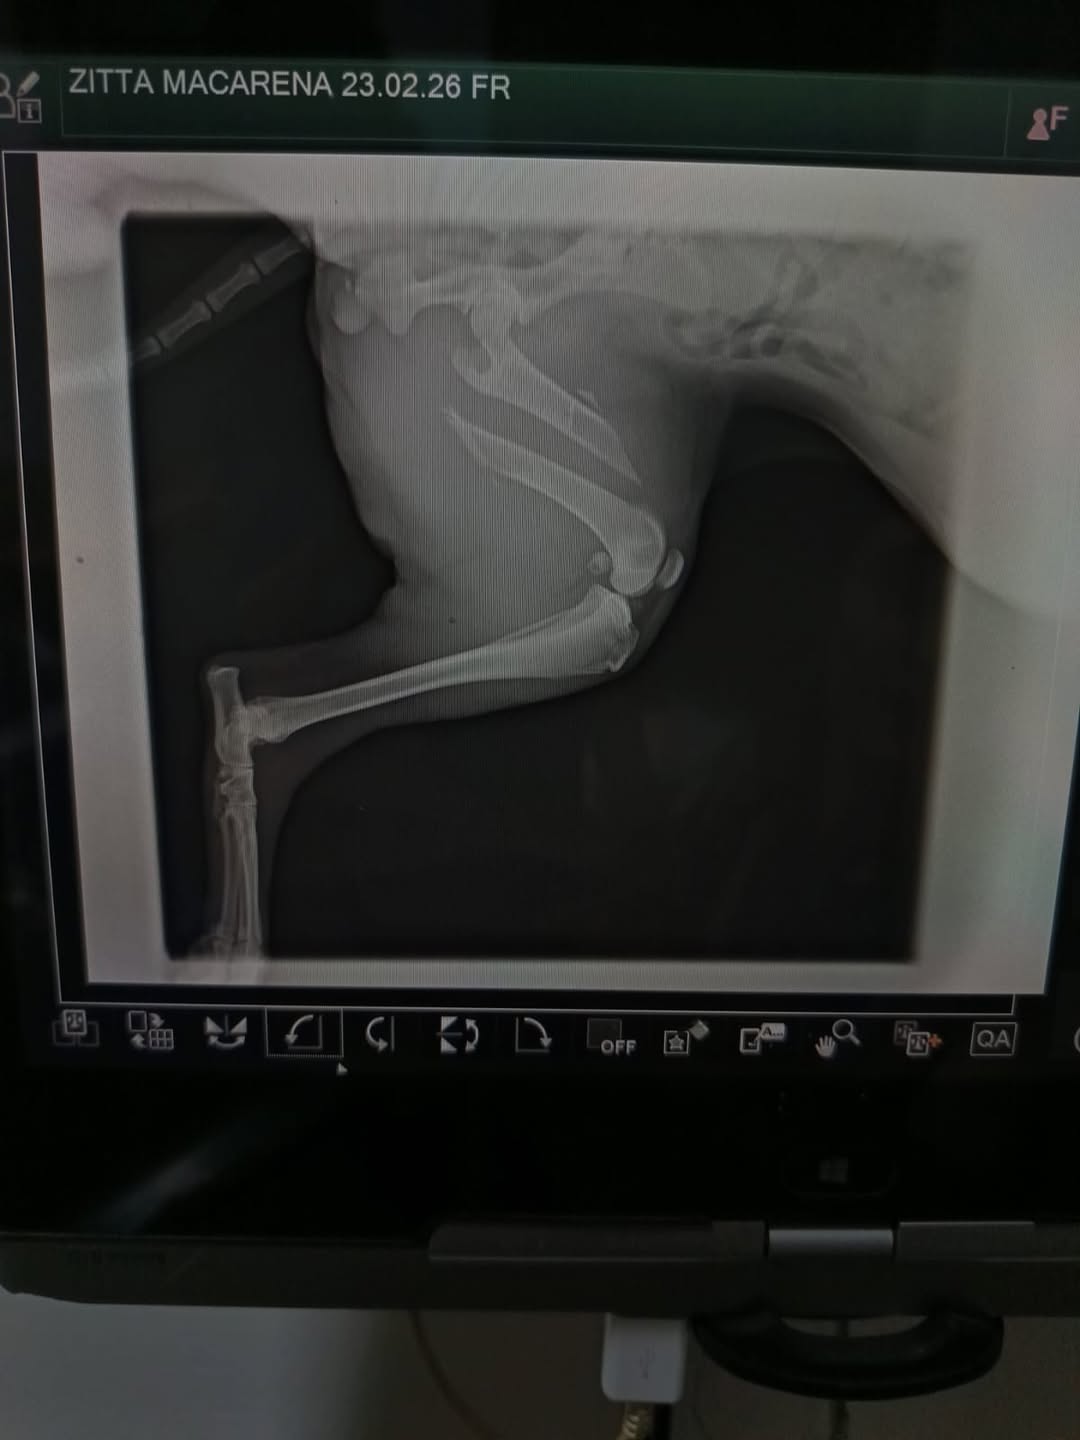

Un hombre fue detenido en La Plata tras comprobarse que mantenía a su perra con una fractura expuesta, sin tratamiento y con un avanzado cuadro de infección. El animal llevaba varios días en ese estado, con bajo peso y sin atención veterinaria.

El acusado fue indagado en el marco de una causa por maltrato animal. Desde la entidad proteccionista pidieron colaboración económica para afrontar los gastos médicos (alias: Rescatistaslp.mz, a nombre de Zitta Macarena) y convocaron a vecinos a ofrecerse como hogares de tránsito para poder continuar con los rescates.